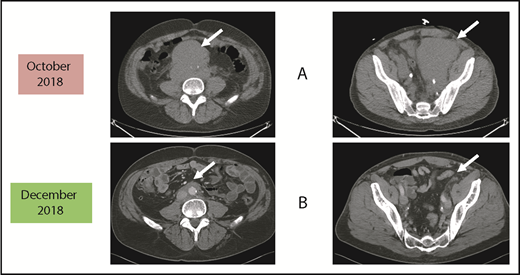

Before and after 3 months of acalabrutinib. A 54-year-old man was diagnosed with stage IVB MCL in 2014. He received chemoimmunotherapy including cytosine arabinoside and an adjuvant autologous SCT. (A) In 2018, he relapsed with left leg swelling due to bulky pelvic disease and a new deep vein thrombosis. (B) After biopsy proof of relapsed MCL, he received acalabrutinib 100 mg twice daily, rituximab, and apixaban; within 3 months, he achieved a marked response with no side effects of the combination. He has returned to full-time work and continues on therapy as of January 2019.

As reported in the clinical trial,43 acalabrutinib at the recommended dose of 100 mg twice daily is well-tolerated as demonstrated by only 1.6% of patients requiring dose reductions and only 6.5% of patients discontinuing acalabrutinib due to adverse events. Of note, atrial fibrillation was not observed in any patient. The most common side effects were headaches (36%) and diarrhea (38%), both of which were typically grades 1-2 and self-limited.43,44 If treatment of these is needed, then oral nonnarcotic agents that do not impair platelet function are recommended. These would include acetaminophen alone or with caffeine. Bleeding events were usually grade 1-2 and consisted of bruising and petechiae; there was 1 case of grade 3 gastrointestinal hemorrhage. Significant myelosuppression can occur and grade 4 neutropenia occurred in 6%. For these grade 3/4 toxicities, dose reductions to 100 mg daily may be required. It is not known what effect dose reduction has on tumor response. In patients such as the 1 described in Figure 1, acalabrutinib at full dose can be given with direct oral anticoagulants with appropriate instructions to watch for bleeding complications.